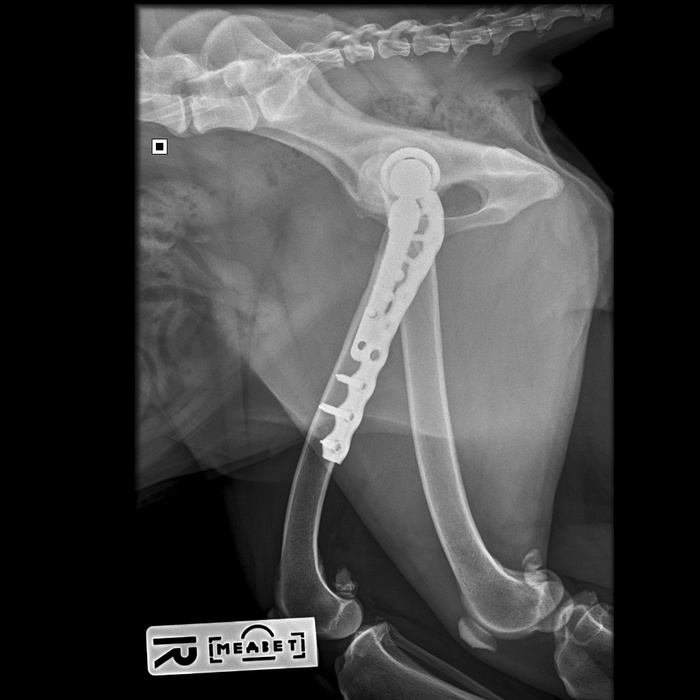

Вот как теперь выглядит ее внутренний мир